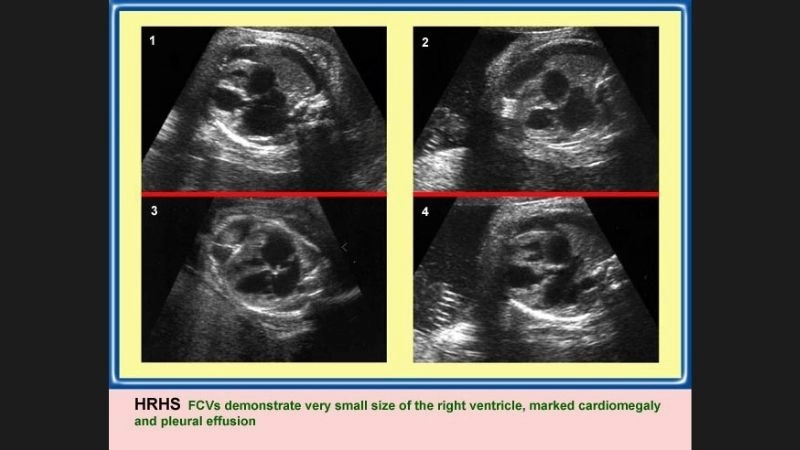

Images visual examples of hypoplastic right heart syndrome (HRHS)

Hypoplastic right heart syndrome (HRHS) is a rare congenital heart defect where the right side of the heart is underdeveloped, impairing blood flow to the lungs.